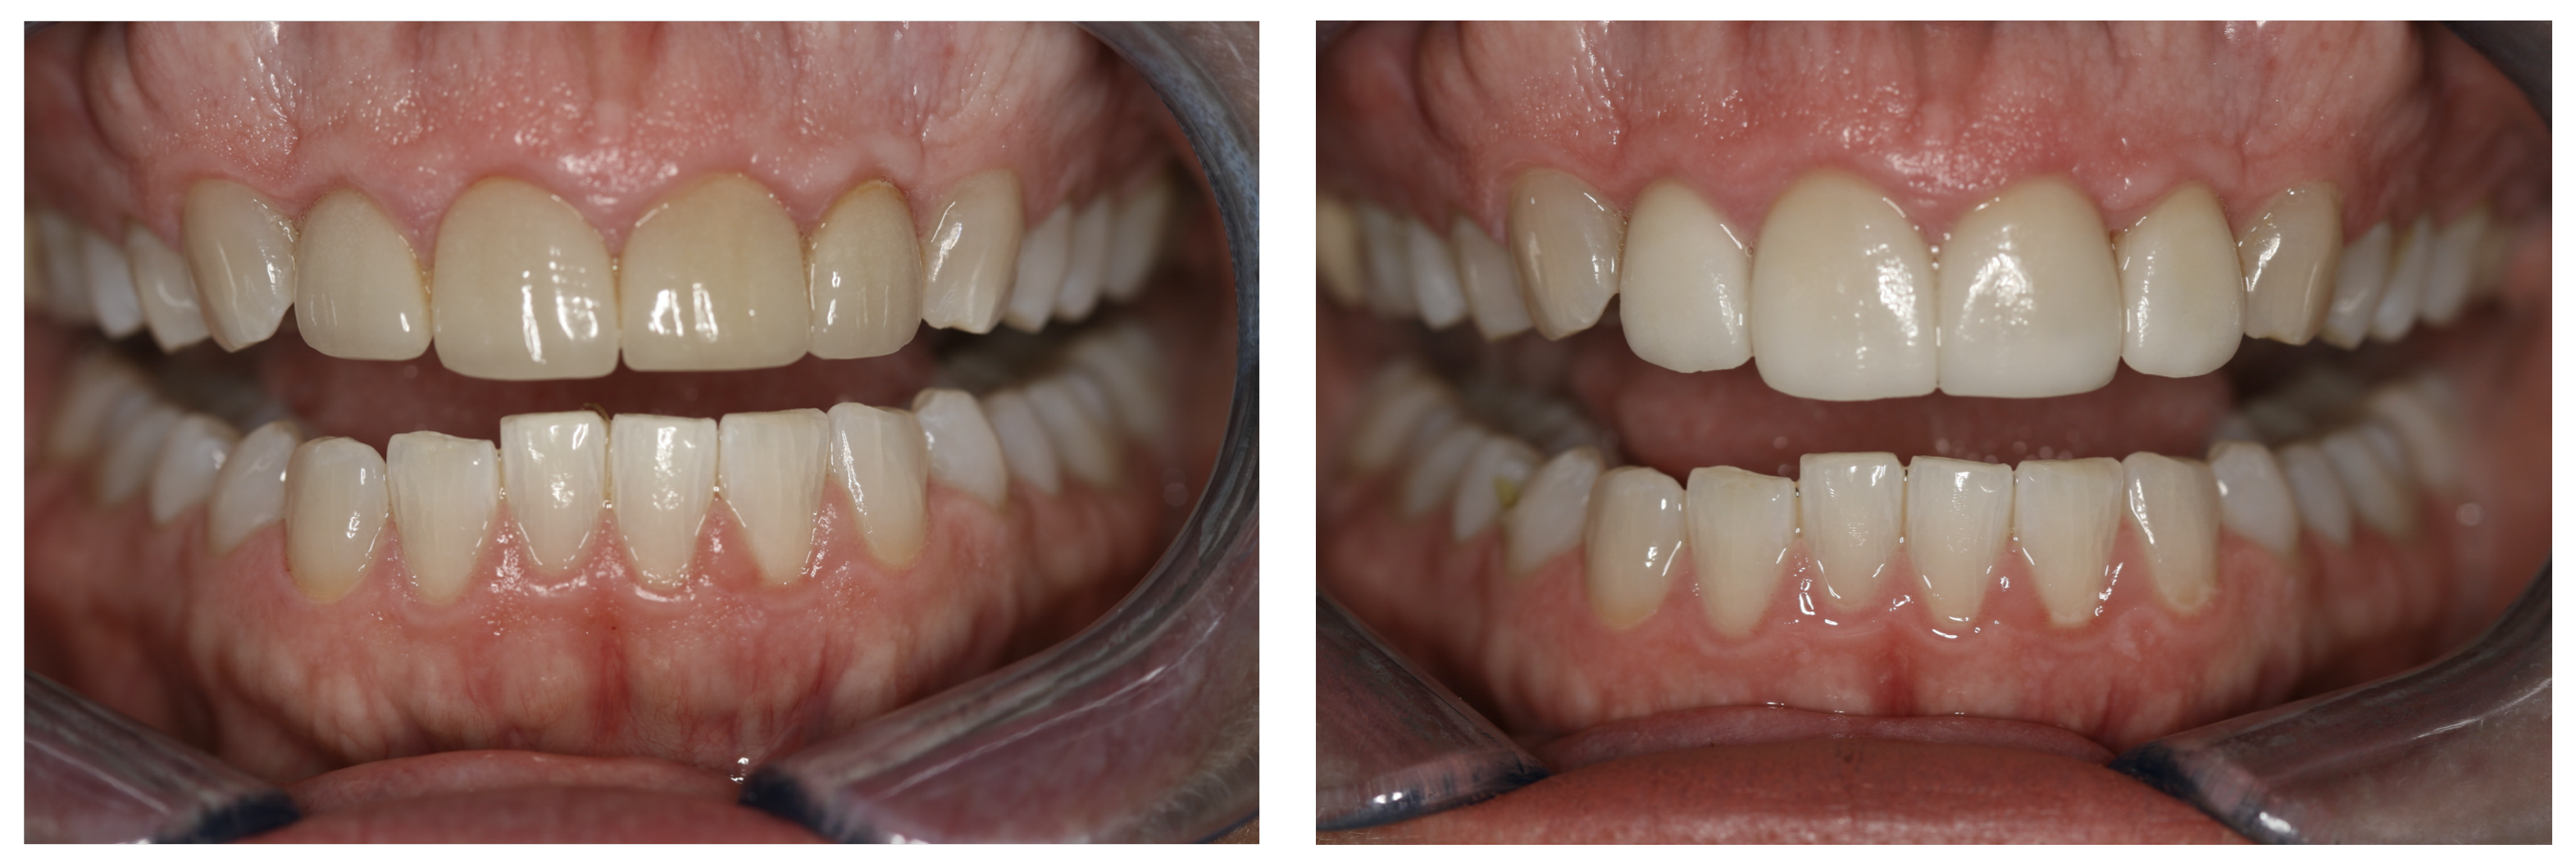

For the case in Figure 9 through Figure 11, the patent presented for an initial consultation with bonding completed on teeth Nos. 7 through 10 a few years prior with a chief complaint of not liking the way the resin bonding looked and how it was wearing. Up to this point, the bonding had repeatedly chipped and been repaired three times already. The patient's canines also exhibited signs of incised wear and flattening, which she did not like. Based on the patient's goals for her smile and her financial budget, she elected to have porcelain veneers completed on teeth Nos. 6 through 11. The total esthetics of the case design were somewhat limited given that the patient's esthetic zone included her posterior teeth and mandibular anterior teeth. Therefore, the color and characteristics of the veneers had to match her existing dentition closely.